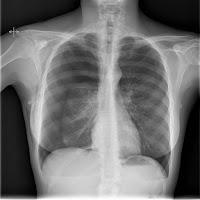

1.- En esta ocasión, una imagen vale más que mil palabras.

1)neumotorax

ResponderEliminar1) Neumotórax + Enfisema subcutáneo.

ResponderEliminarBueno, respecto a este caso mencionar el origen traumático como causa probable (fractura clavicular y de la 8º costilla derecha, si no cuento mal, jeje!).

Aumentando la imagen se observa además línea de neumotórax izquierdo, que en un primer momento había pasado por alto.

ResponderEliminarPor aclarar alguna duda, decir que el paciente acudió al Servicio de Urgencias por dolor en hemitórax derecho, de aparición brusca y sin referir historia de antecedente traumático.

1.- Neumotórax derecho + enfisema subcutáneo (por lo que dice Silvia seguramente espontáneo).